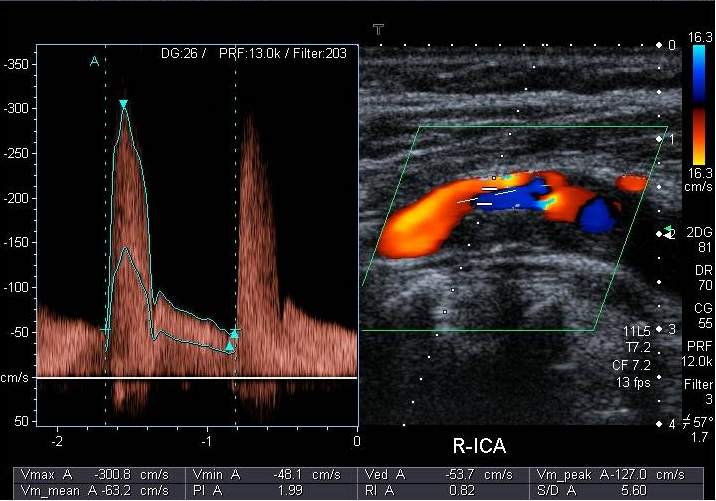

In the majority of the cases, stroke is causes by the atherosclerotic lesion of the supplying arterial system of the brain. Ultrasound examination can reliably depict a long segment of the four main extracranial large vessels supplying the brain. Fortunately, most atherosclerotic lesions that causes cerebrovascular symptoms are to be found in the carotid bifurcation and therefore they can be well diagnosed on carotid US examinations. Besides depicting plaques, US can measure their size and assess their composition. Lipid-rich plaques that are covered with a thin, easily rupturing fibrotic cap are considered instable, but inhomogeneous structure and irregular surface are also a poor prognostic factor. Exulceration, a consequently appearing excavation on the surface of the plaque carries the highest risk for embolization. Color Doppler examination can help precisely define the contours of plaques. It can clearly depict the residual lumen of the narrowed arterial segment and it is able to confidently differentiate between complete obstruction from high grade stenosis. Contrast enhanced ultrasound examination can show the angiogenesis at the basal part of instable plaques as well as MRI examination. One of the main diagnostic goals of cerebrovascular imaging is to determine the grade of stenosis of the internal carotid artery, since the risk of stroke grows parallel with the grade of the stenosis, which can be avoided with reconstructive surgery or with stent implantation. A 50% diameter decrease is considered the limit at which point a stenosis counts as hemodynamically significant. Below this the grade of stenosis can be well estimated with 2D planimetric measurements. Above this level stenotic lesions are quantified by their hemodynamic effect, based on the measurements of flow velocity increase. If a significant stenosis is discovered, the patient must be closely followed. At a stenosis of about 70% surgical or interventional procedure should already be considered. In these cases, or when diagnosis is equivocal, it is important that the duplex sonography is followed by an imaging method that can visualize the cerebrovascular system in full.

Image

Duplex ultrasonography with targeted Doppler measurement

Contrast enhanced MR-angiography

Fig. 14., 15.: Arteria carotis interna stenosis